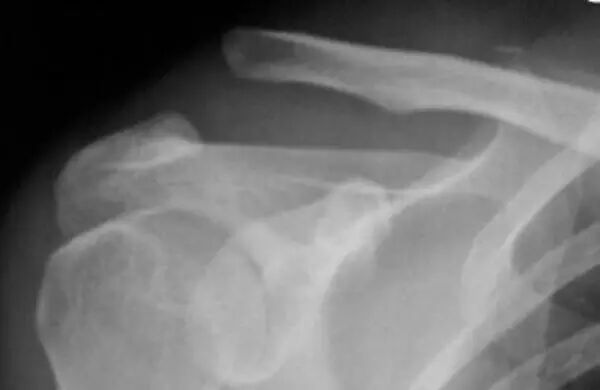

来源:好医生在线